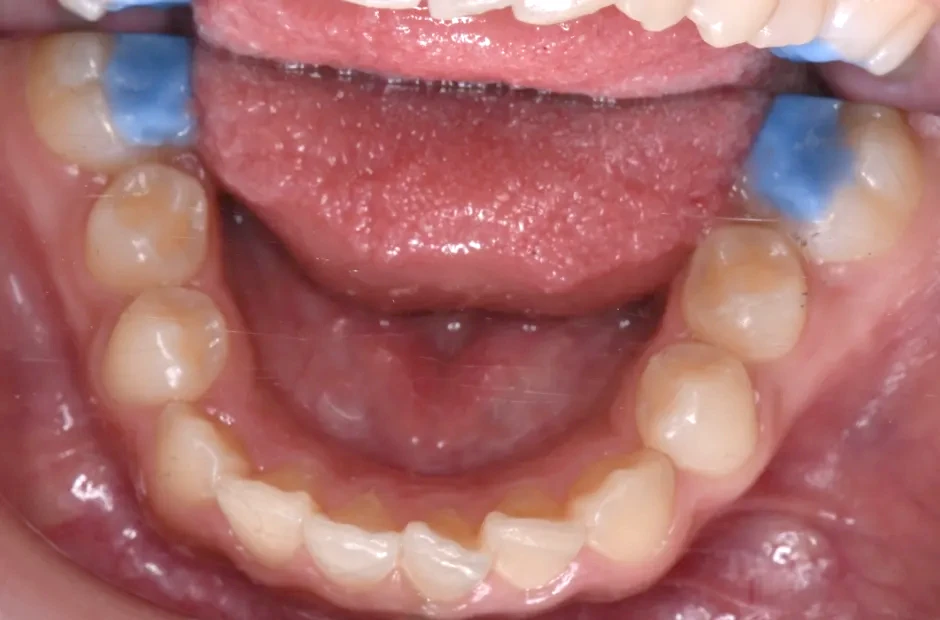

反対咬合

| 診断名・主訴 | 前歯反対咬合 |

|---|---|

| 年齢・性別 | 12歳・男性 |

| 治療期間・回数 | 1年半 18回 |

| 治療に用いた主な装置 | リンガルアーチ(前方誘導弾線) |

| 抜歯部位 | なし |

| 治療費 | 35万円(税抜) |

| リスク・副作用 | 装置による違和感・疼痛・歯肉退縮・歯根吸収・虫歯のリスクなど |